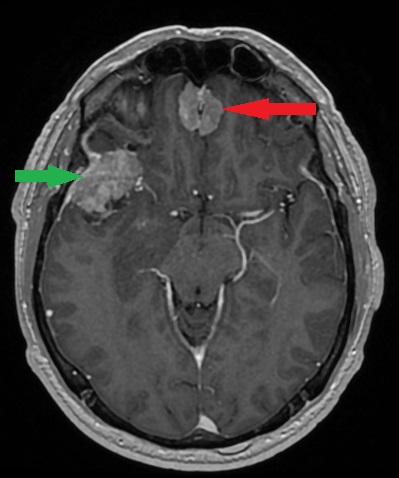

- Zmiany naczyniowe (np. naczyniaki jamiste, tętniaki)

- Zmiany infekcyjne (np. ropnie, gruźlica, zakażenia grzybicze, pasożytnicze)[1–4]